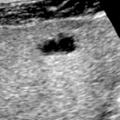

Nodule typique de CHC sur foie de cirrhose

TUMEURS DU FOIE